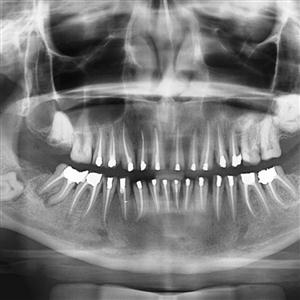

DIRECT DIGITAL OPG

Direct Digital OPG = Special Panoramic x.ray of upper and lower teeth, mandible and T M Joints in single x.ray film by special dedicated OPG Machine.

We are using World-class Carestream Equipment 8000 C Direct Digital OPG (The first one in Saurashtra installed in 2010) with which we can take OPG film within 20 seconds in single shot. The machine produces the image directly on the monitor without cassette or screen.

This technology produces best images for better diagnosis with great patient comfort and user friendly approach.

Prescribed by Dentists, ENT Surgeons, Plastic / Maxillo-facial Surgeons and Onco Surgeons.